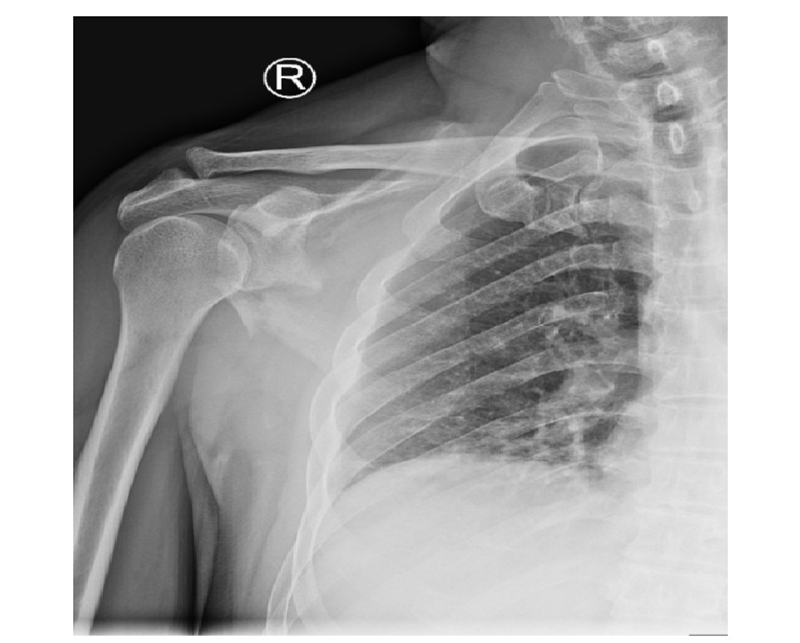

病例4为53岁男性患者,因高处坠落导致右肩胛骨骨折,合并右侧第3、5、7、8肋骨骨折(图20-21)。

图20 术前X线片示肩胛颈及肩胛骨体部骨折